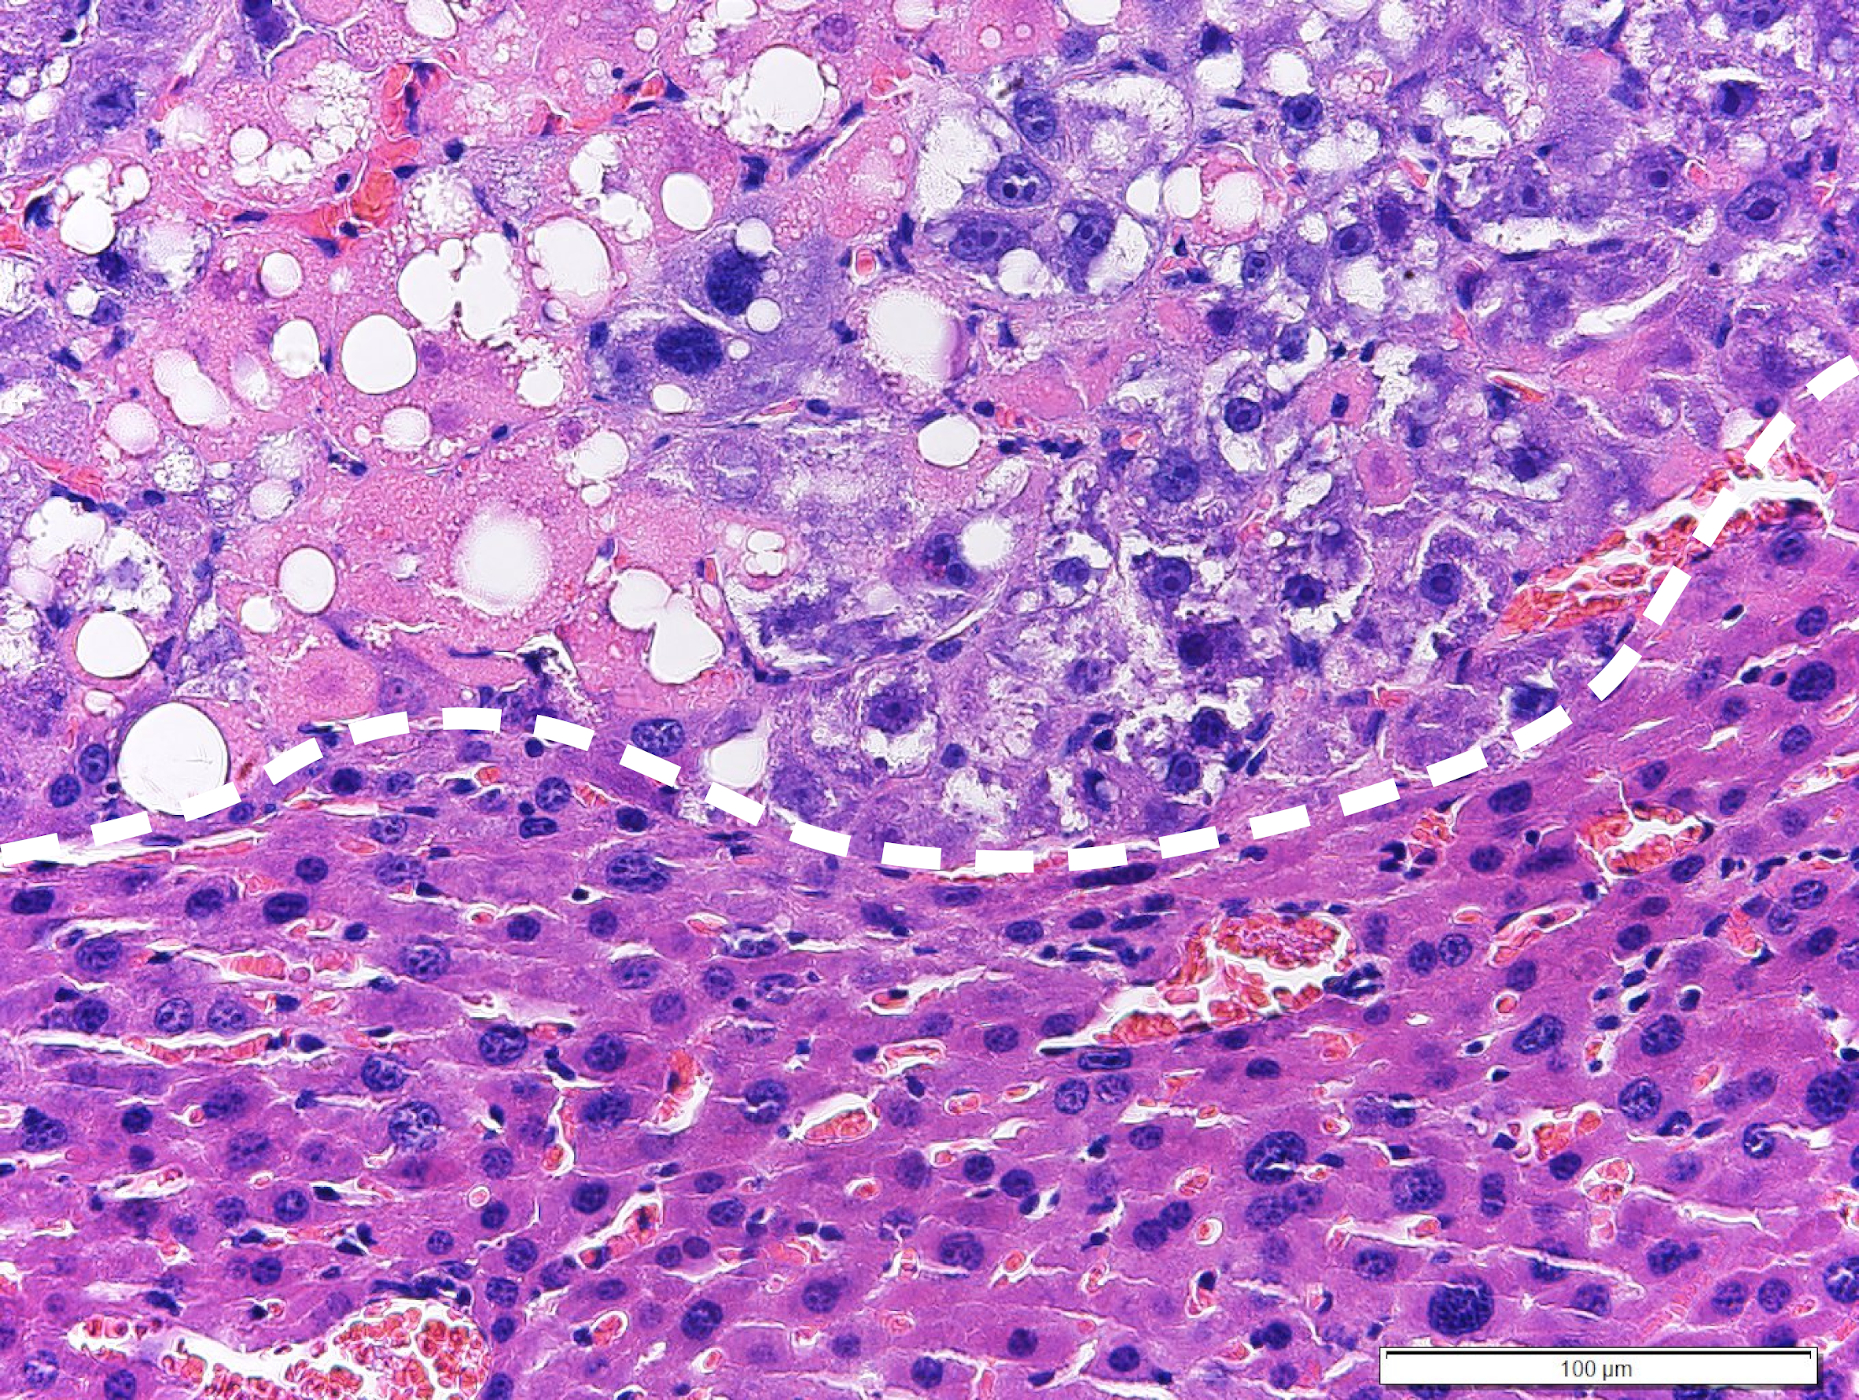

Beim neuen Ansatz wird therapeutisch in den Fettstoffwechsel der Tumorzellen eingegriffen. Durch Aktivierung des sogenannten LXRα Proteins kommt es zu einer Steigerung der Fettsäuresynthese. Diese kann zunächst von der Tumorzelle toleriert werden, weil anfallende gesättigte Fettsäuren (aus der Ernährungsmedizin auch als schlechte Fettsäuren bekannt) kontinuierlich durch das Enzym Stearoyl-CoA desaturase-1 (SCD1) zu ungesättigten (guten) Fettsäuren umgewandelt werden.

Wird jedoch gleichzeitig ein zweites Protein, die sogenannte Raf-1 Kinase, gehemmt, so kommt es in der Tumorzelle zu einer Anreicherung von gesättigten Fettsäuren, welche von der Tumorzelle nicht toleriert werden kann und zum Zelltod der Tumorzelle führt. Von besonderer Bedeutung ist die Tatsache, dass das neue Therapiekonzept eine starke Wirksamkeit gegen Leberkrebs hat, welcher durch Leberverfettung (NASH) hervorgerufen wird. Klinische Studien haben gezeigt, dass diese sogenannten NASH-HCCs mit derzeit verfügbaren zielgerichteten oder Immuntherapien nur schwer zu beherrschen sind.